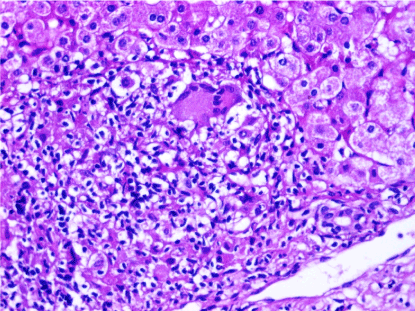

Figure 2. A case of autoimmune hepatitis, showing infiltration by mononuclear cells including scattered plasma cells (arrow) (H&E stain,X400)